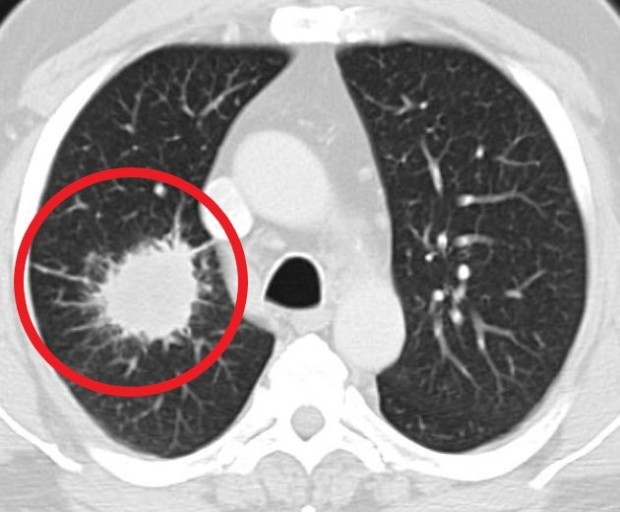

- 정기적인 건강 검진: 특히 흡연자나 가족력이 있는 경우, 저선량 흉부 CT와 같은 정밀 검진을 통해 조기에 발견해야 합니다.